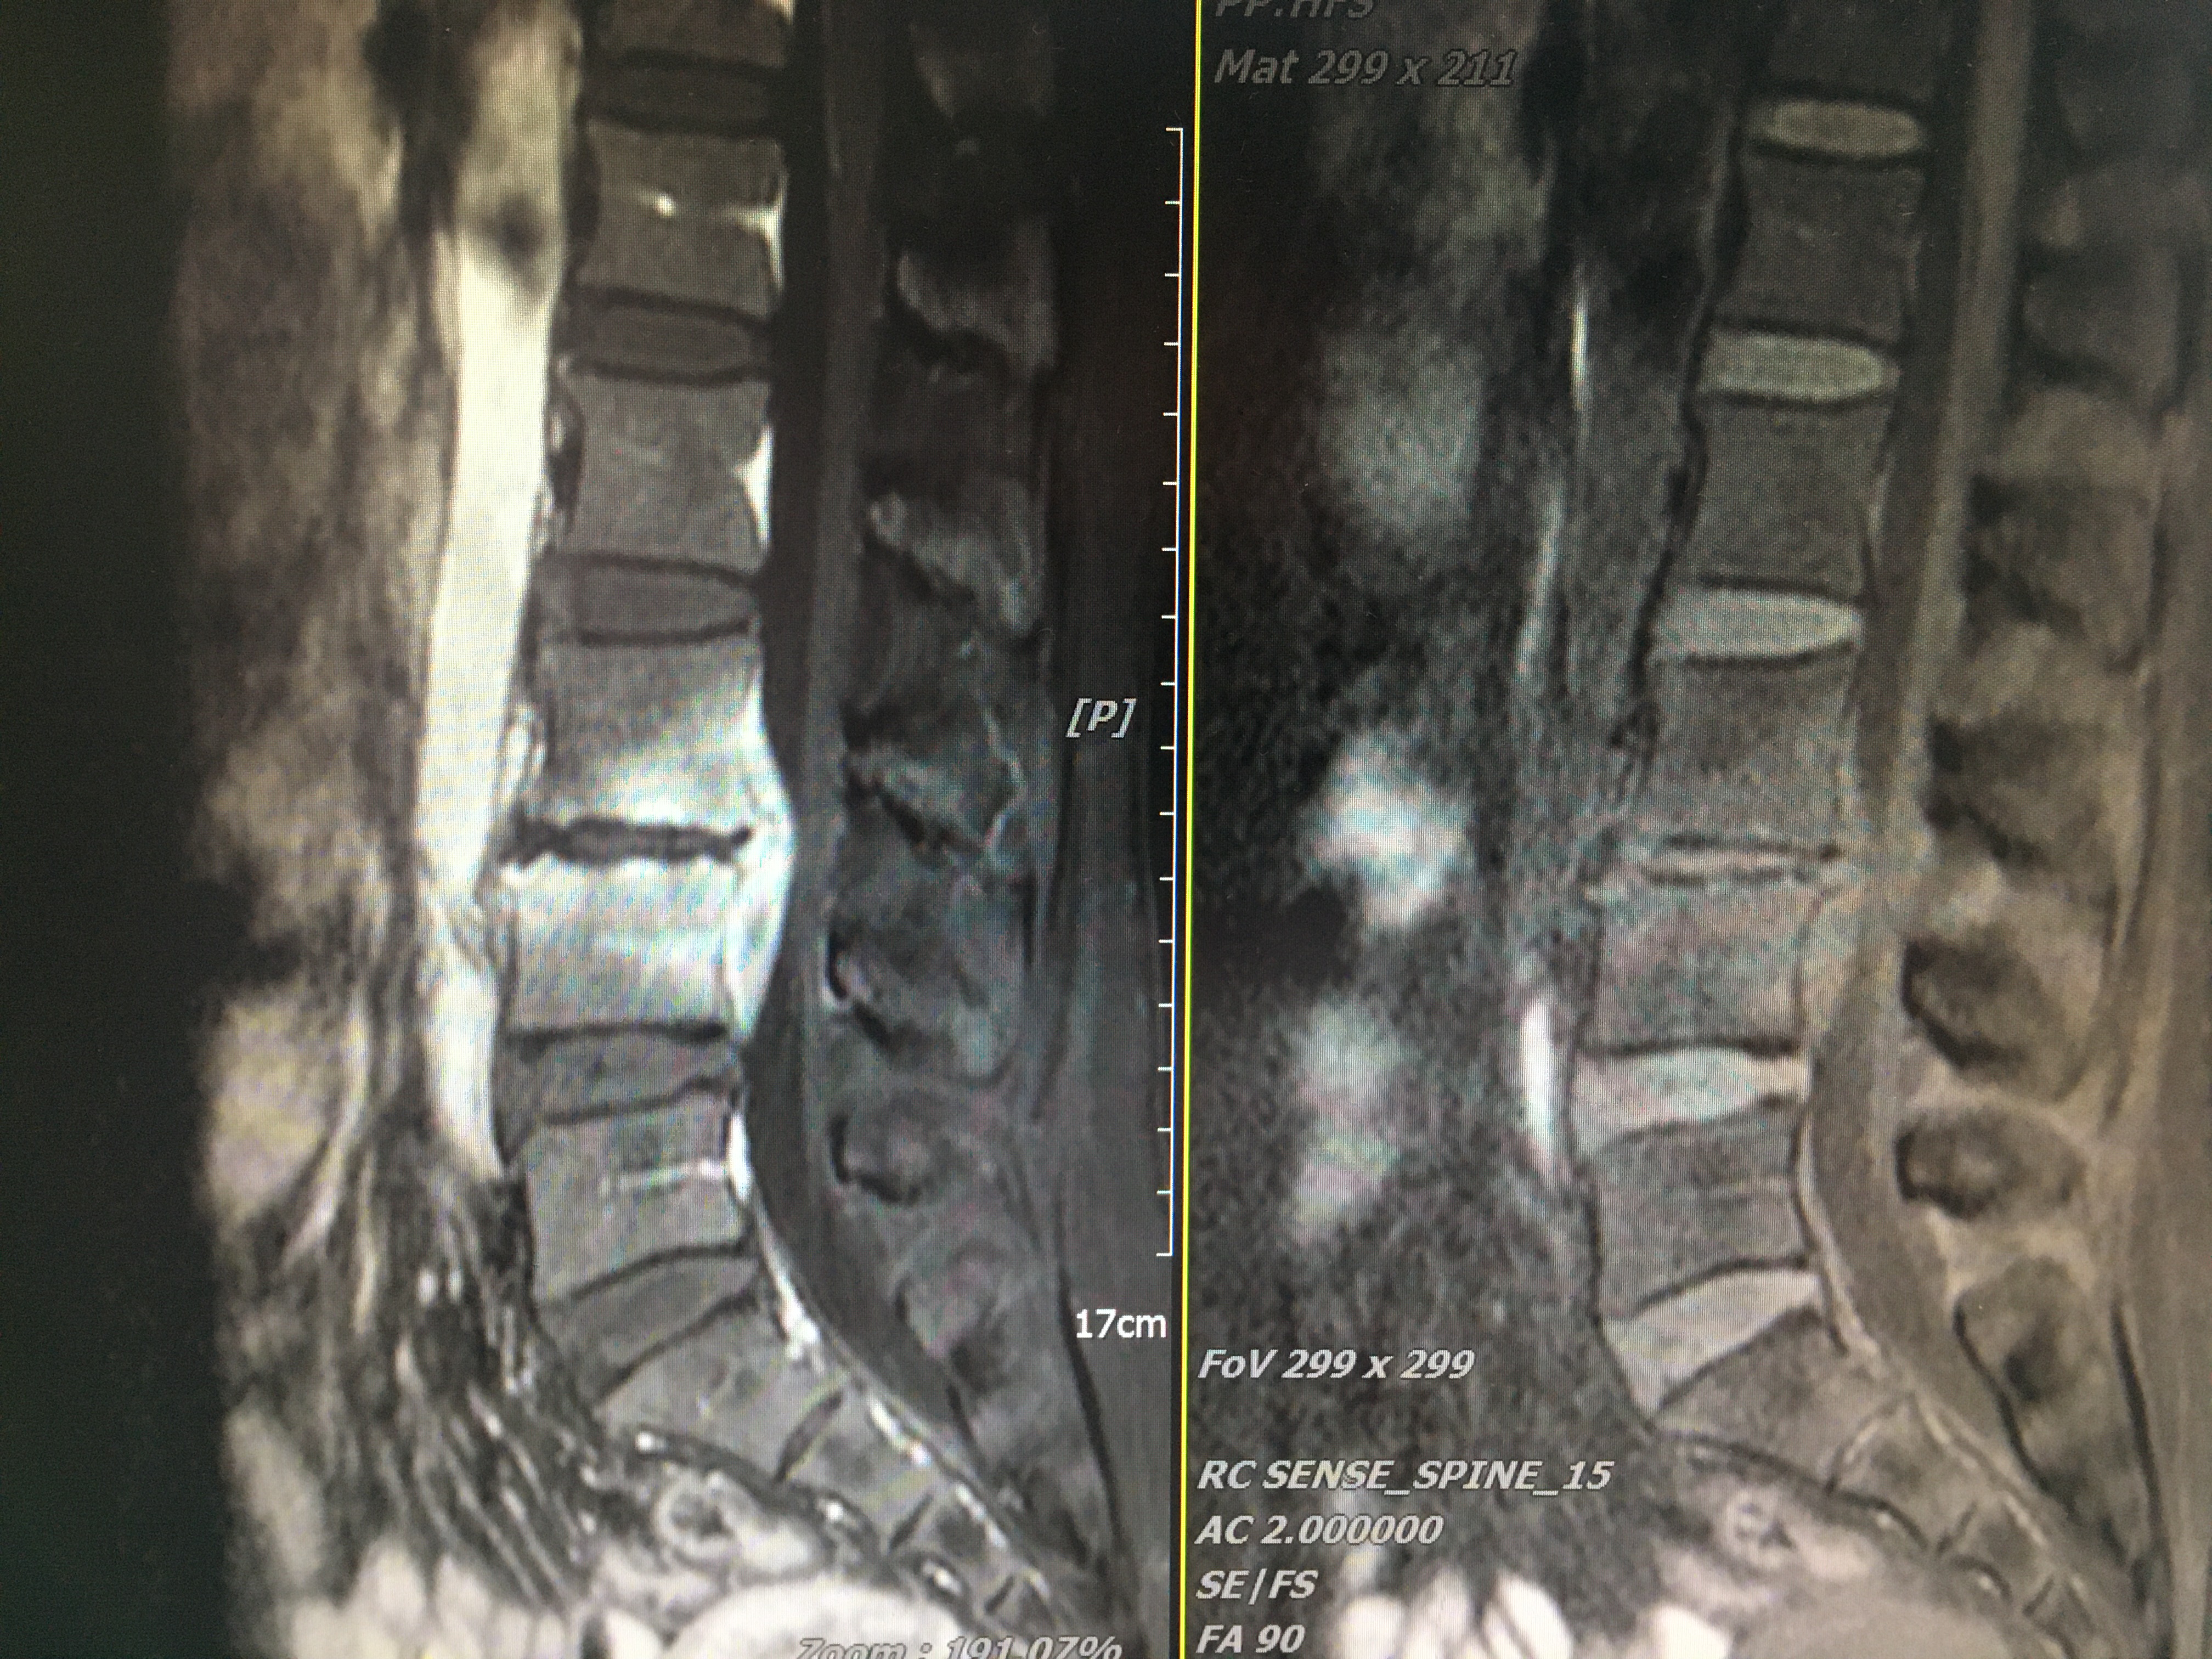

48歲陳姐原本身姿挺拔,體態(tài)優(yōu)美,一個(gè)月前出現(xiàn)持續(xù)的腰痛,到漳州市中醫(yī)院就診后發(fā)現(xiàn)病情遠(yuǎn)比想象的嚴(yán)重,經(jīng)X線、CT、MRI檢查回報(bào)考慮:脊柱感染(腰3-4):細(xì)菌感染?結(jié)核?布什菌感染?完善炎癥及結(jié)核特異性檢查,也未能明確感染原因,這給治療用藥帶來(lái)很大困難。

術(shù)前MRI

脊柱感染椎管內(nèi)膿腫,傳統(tǒng)手術(shù)采用后路減壓+后路置釘。缺點(diǎn):手術(shù)創(chuàng)傷較大、病灶清除相對(duì)不徹底、植骨面積小、存在膿液向椎骨內(nèi)擴(kuò)散等風(fēng)險(xiǎn)。經(jīng)科室疑難病例討論后,一致同意采用:經(jīng)斜外側(cè)入路(Olif入路)微創(chuàng)腰3-4病灶清除+取同側(cè)髂骨椎間植骨+后路天璣機(jī)器人導(dǎo)航下經(jīng)皮微創(chuàng)腰3-4椎弓根釘系統(tǒng)內(nèi)固定術(shù)。手術(shù)在陳志伸、李毅嵩專家團(tuán)隊(duì)及麻醉、護(hù)理、機(jī)器人操控團(tuán)隊(duì)緊密配合下順利完成,術(shù)中出血量約150ml。